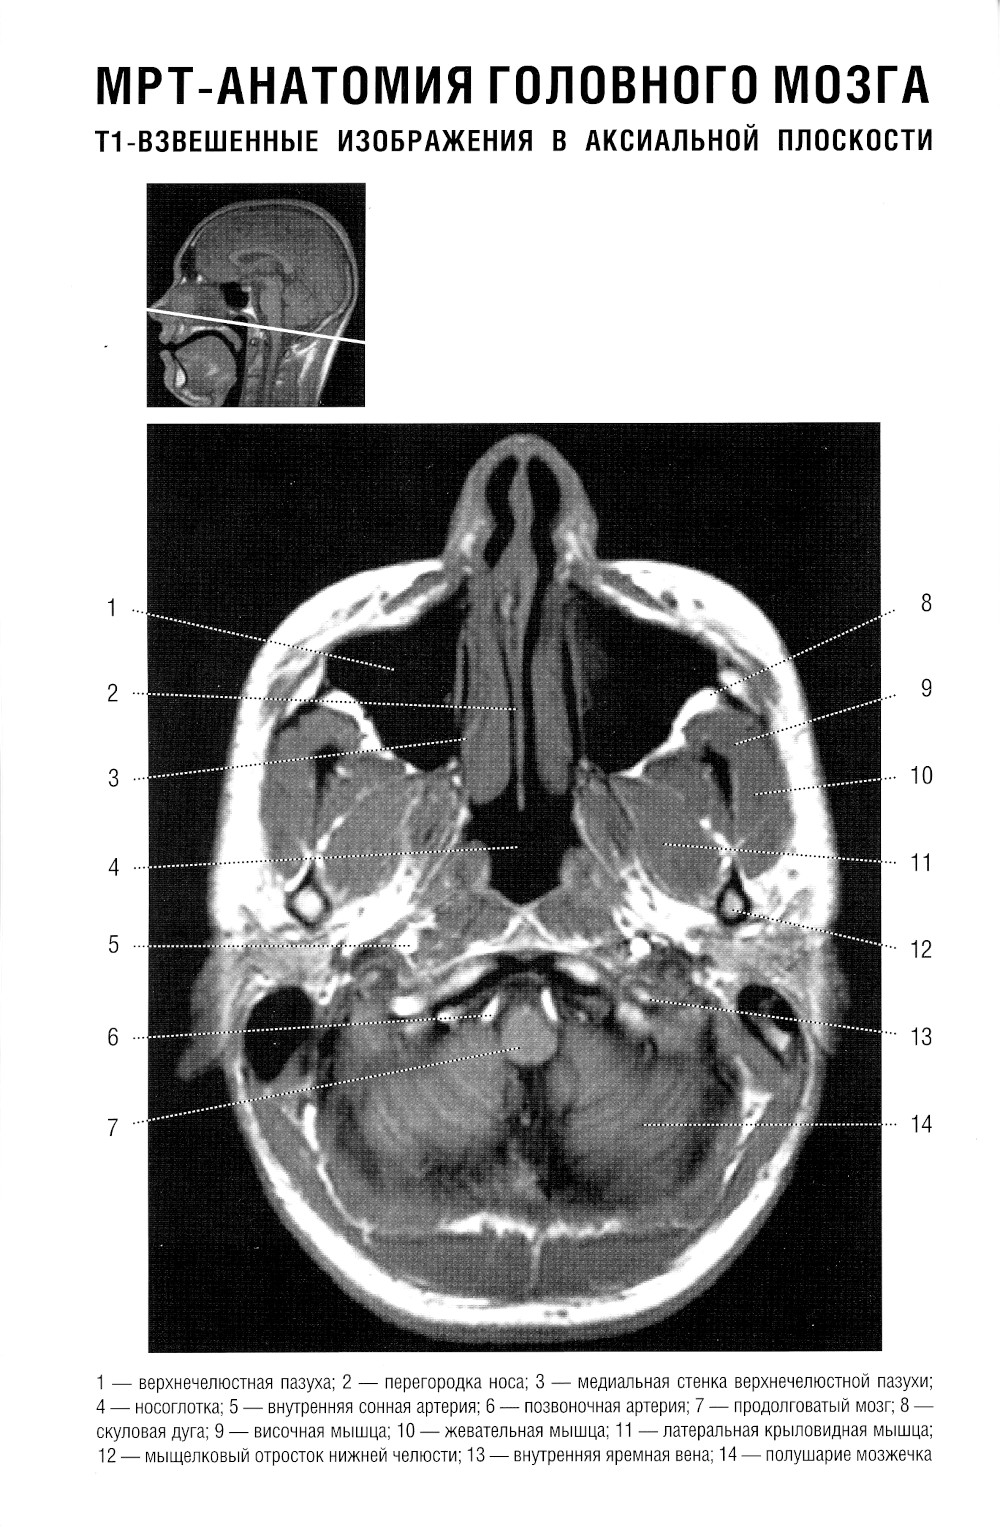

В руководстве представлена нормальная анатомия головного мозга и позвоночника по данным МРТ- и КТ-исследований. MPT-изображения головного мозга отражены в трех взаимно перпендикулярных плоскостях. Отдельная глава посвящена визуализации и нормальной анатомии сосудов головного мозга, в том числе с изображениями, получаемыми при бесконтрастной магнитно-резонансной ангиографии. Для врачей-рентгенологов, специалистов КТ и МРТ, невропатологов, нейрохирургов, а также врачей смежных специальностей. Руководство рекомендовано для обучения студентов медицинских вузов, а также может использоваться в системе последипломного профессионального образования.| Издательство | Элби |